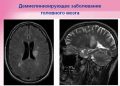

Хочу стать мамой в фокусе рассеянный склероз